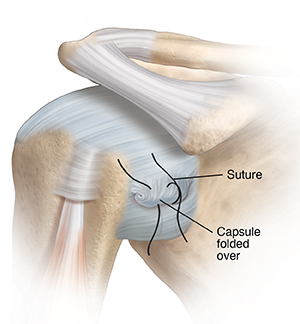

Stretched capsule

A stretched capsule will often stay loose. A loose capsule can’t hold the joint firmly in place. The bones of the joint may feel like they move too much, and the shoulder can dislocate.

During arthroscopy, a stretched capsule is folded over itself and stitched in place. This is done from inside the capsule. This tightens the capsule, helping make the shoulder joint more stable.